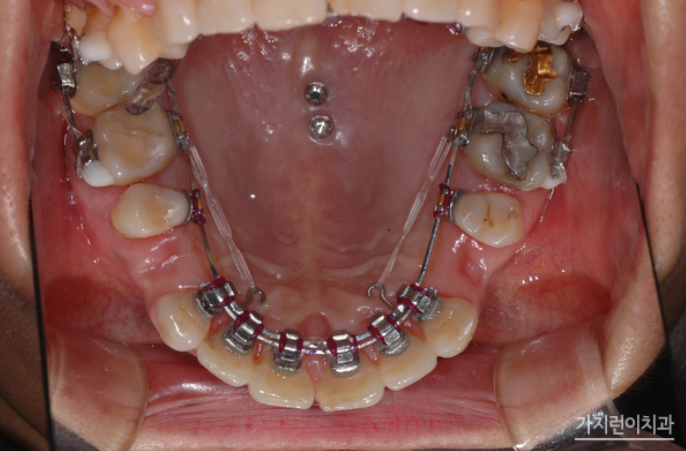

뻐드렁니 교정과 임플란트 계획을 동시에 행해 구치 함입 치료를 시작한 지 5개월이 되었을 때 하악 구치부에 임플란트를 식립했으며 함입치료 7개월 째에 임시크라운을 올릴 수 있었습니다.

두 개의 와이어를 이용한 탄댐설측교정

특히 본원에서는 안정적인 교정을 위해 상악 설측교정 장치는 두 개의 와이어를 사용하는 탄댐설측교정을 진행했습니다. 교정과 임플란트를 병행 했음에도 결과를 보면 안정적인 구치부 교합을 만들었다는 것을 확인할 수 있었는데요. 임플란트는 고정이 되기 때문에 교정이 아주 약간만 틀어져도 틈이 벌어지는 등의 문제가 생길 수 있습니다. 그래서 계획대로 치아이동이 잘 되어야 했었는데요. 사진을 보면 지정된 위치에 임플란트가 식립되어 조화로운 치열과 교합 상태로 완성된 것을 볼 수 있습니다.